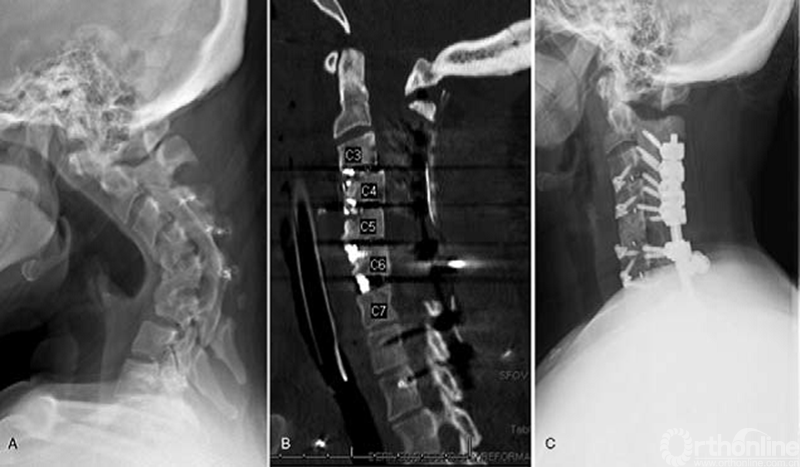

典型病例1(A)术前;(B)术后;(C)随访1年

前路截骨术可以直接减压椎管,解除脊髓牵张,实现畸形矫正。结合前路截骨术,后路截骨术可能以一种更有限的方式进行,减少了并发症发生。因而,联合入路是一种安全有效的颈椎畸形矫正手术方式。